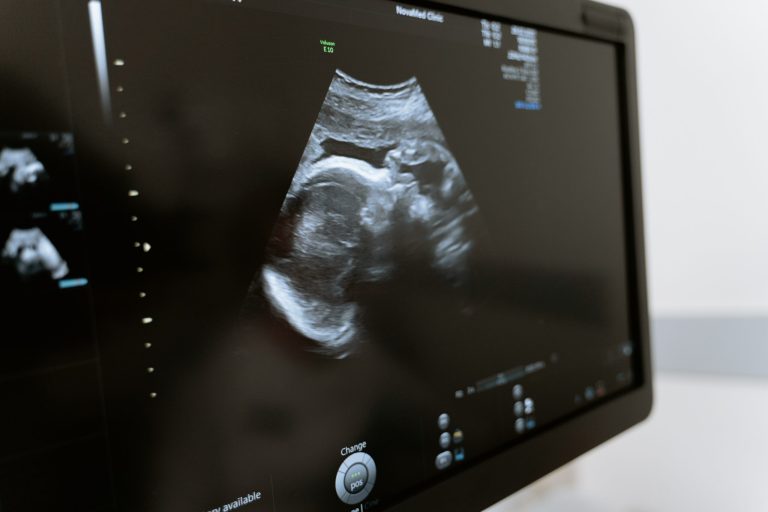

¿Cuándo puede sentir dolor mi feto?

Incluso cuando te encuentras inesperadamente embarazada y estás considerando la posibilidad de abortar, conocer los detalles íntimos de lo que está ocurriendo dentro de tu cuerpo es vital para ayudarte...

¿Cuándo es mi embarazo algo más que un embarazo?

Incluso cuando te encuentres inesperadamente embarazada y estés considerando la posibilidad de abortar, conocer los detalles íntimos de lo que está ocurriendo dentro de tu cuerpo es vital para ayudarte...